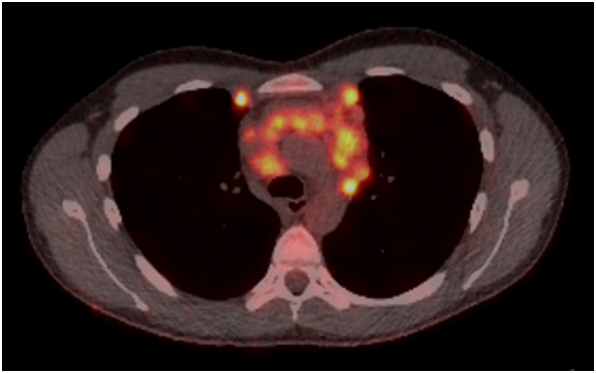

A PET CT scan was subsequently performed. It demonstrated marked metabolic activity, indicating an aggressive process.